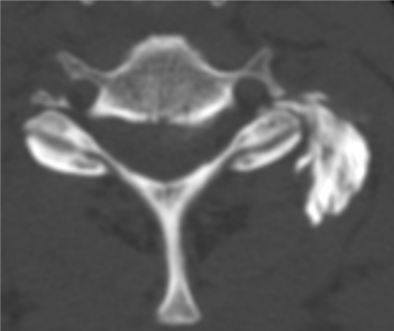

Infiltration du rachis lombaire. Sous contrôle scannographique,le médecin positionne l'aiguille en regard du trou de conjugaison (image a) par lequel sort la racine nerveuse (nerf sciatique). Le contrôle après injection (image b) s'assure de la diffusion du produit.